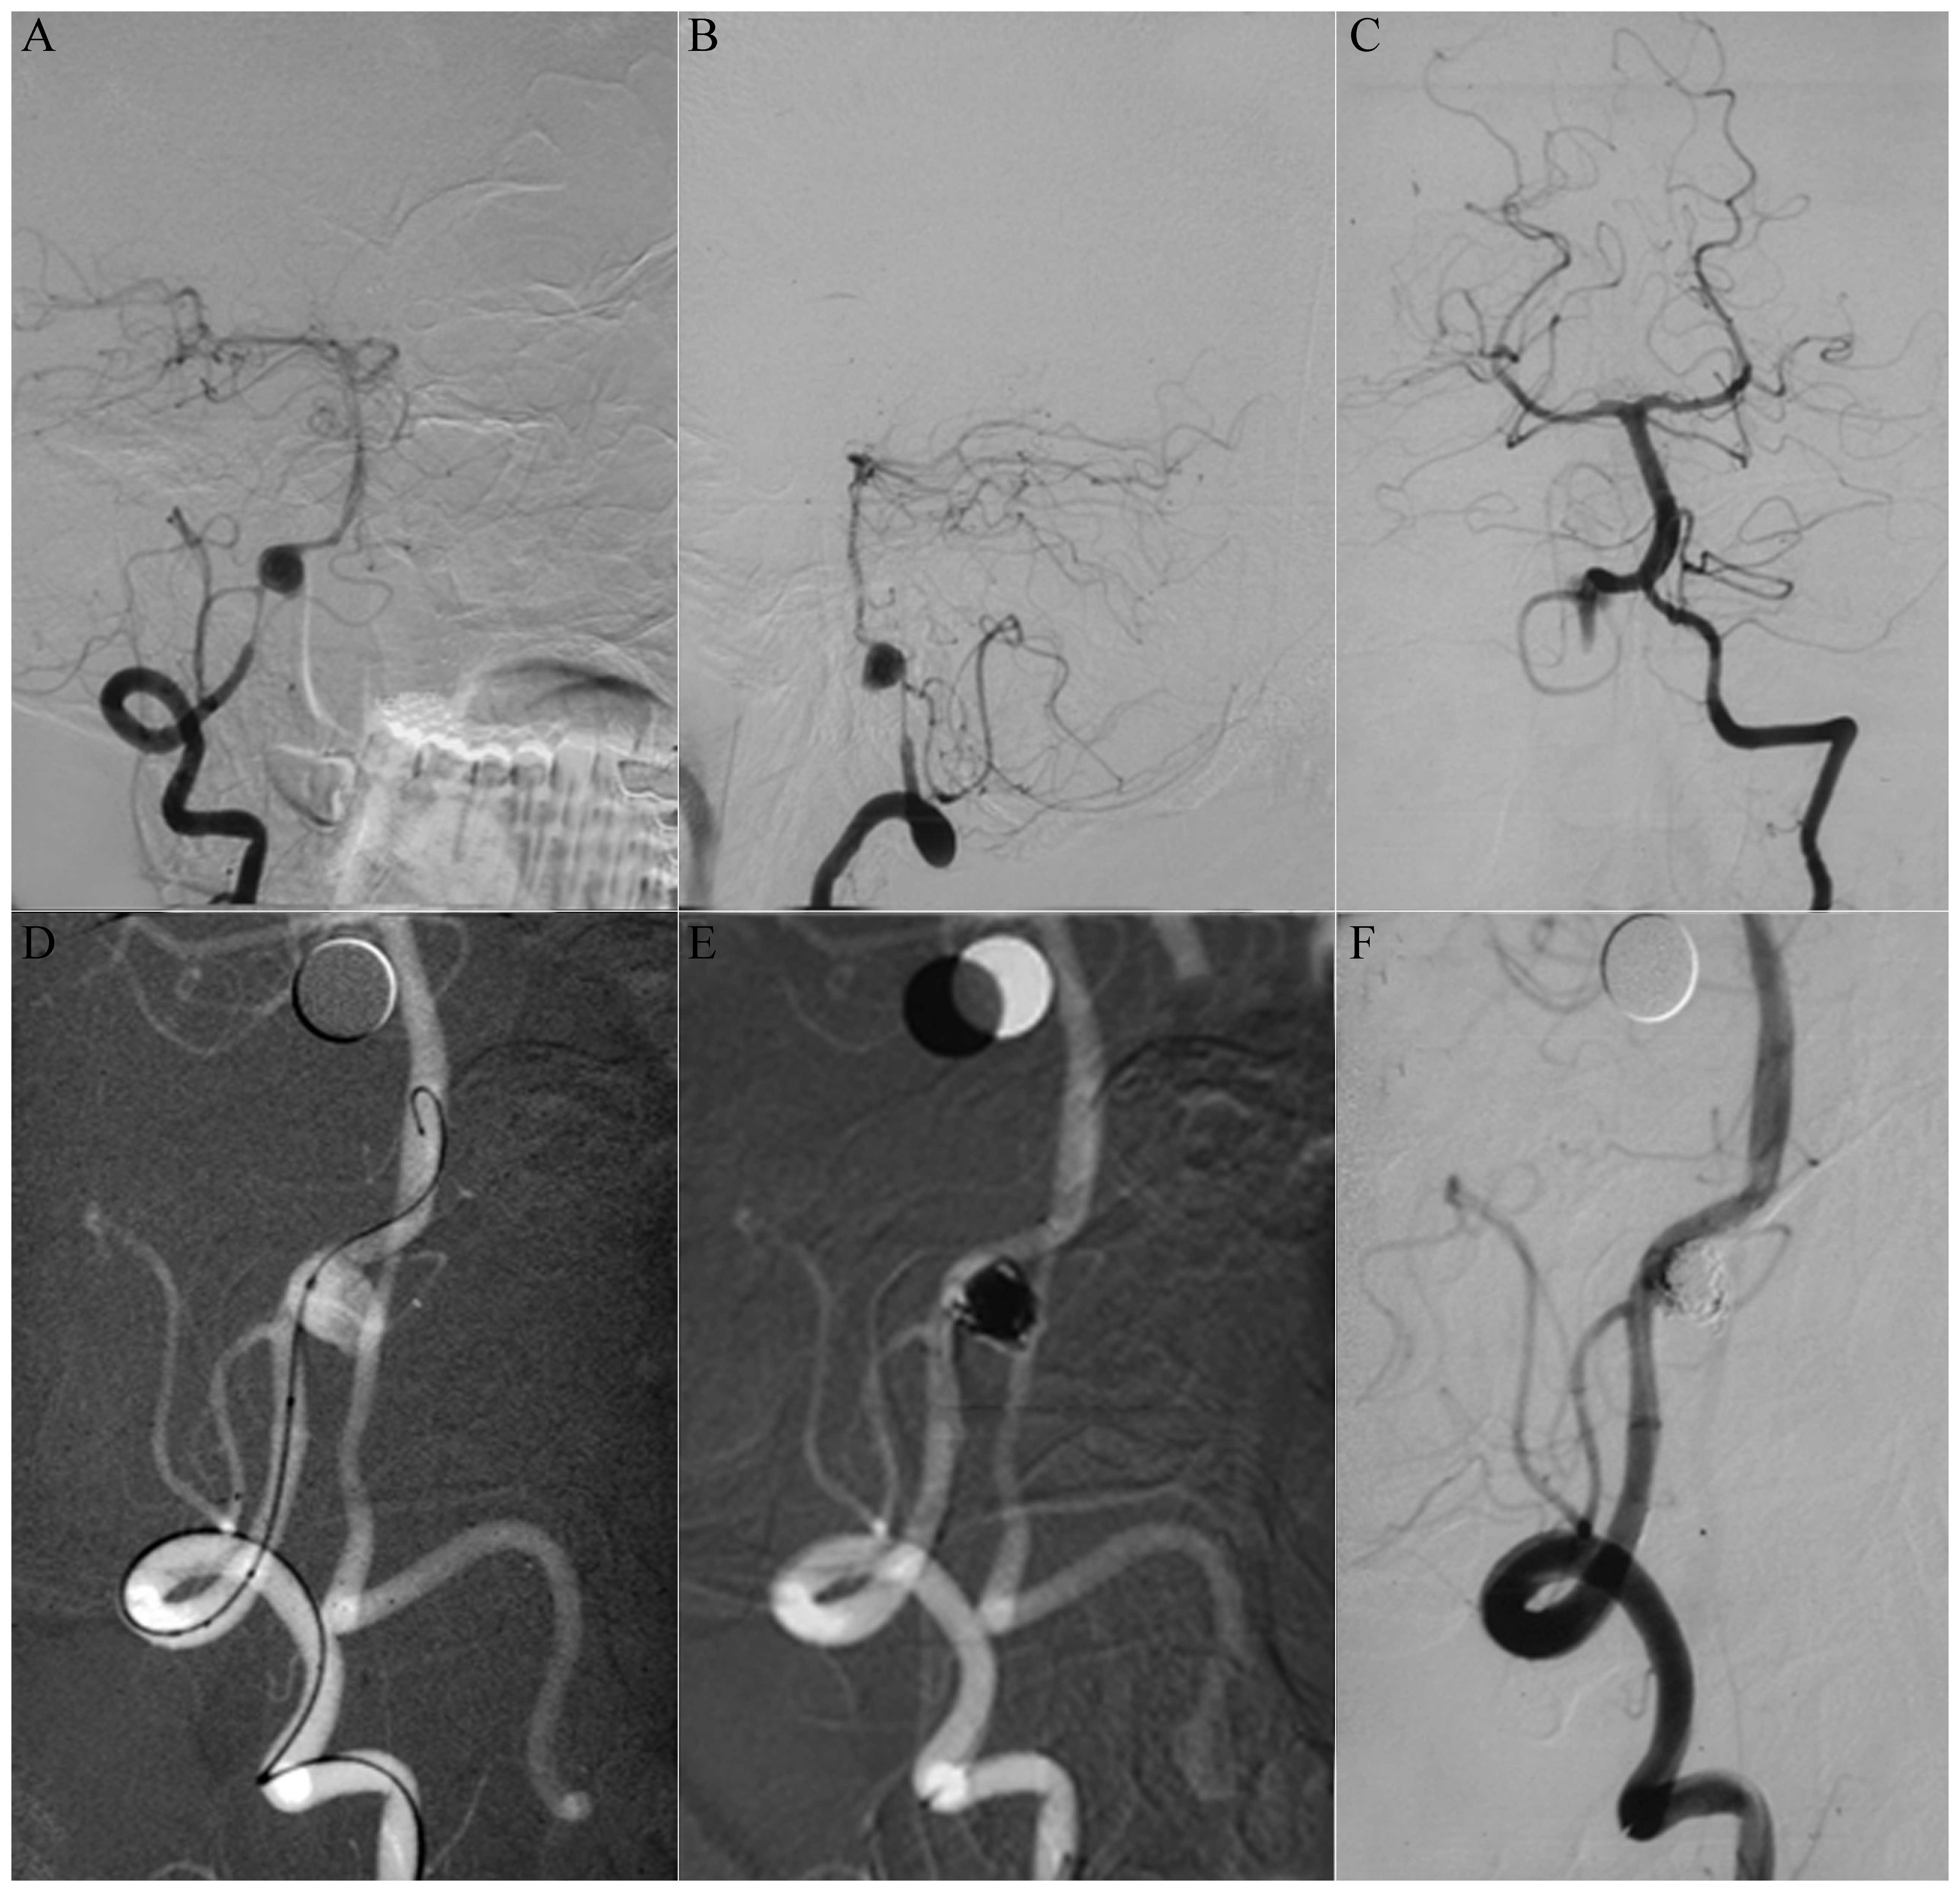

Among the 10 patients with type I aneurysms, four patients with type Ia received coiling with parent artery occlusion (Fig. 1), one patient with type Ia received stent-assisted coiling, three patients with type Ib received stent-assisted coiling (Fig. 2), one patient with type Ib received coiling only and one patient with type Ib was treated conservatively. Among the 13 patients with type II aneurysms, two patients with type IIa received coiling with parent artery occlusion (Fig. 3), five patients with type IIa received stent-assisted coiling (Fig. 4) and all six patients with type IIb received stent-assisted coiling. Among the eight patients with type III aneurysms, four patients with type IIIa received coiling with parent artery occlusion (Fig. 5), one patient with type IIIa received stent-assisted coiling (Fig. 6), two patients with type IIIb received stent-assisted coiling and one patient with type IIIb received coiling only.

Figure 3

(A) Digital subtraction angiography (DSA) and (B) oblique DSA images showing a well-developed type IIa dissecting aneurysm of the left vertebral artery located at the origin of the posterior inferior cerebellar artery (PICA) and the contralateral vertebral artery. (C) DSA image of the right vertebral artery and (D) negative image showing the left vertebral dissecting aneurysm following coiling. The post-treatment angiograms show complete obliteration of the aneurysm, (E) occlusion of the left vertebral artery and (F) the PICA filled with blood from the right vertebral artery.